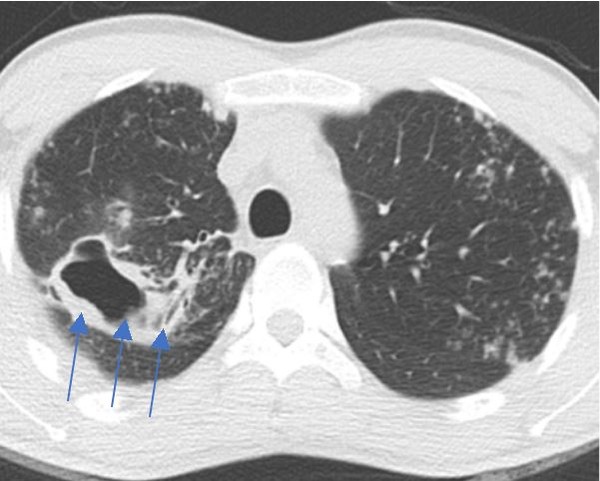

진단은 임상적인 호흡기 증상과 함께 흉부 영상 소견 및 미생물학적 균 확인 등의 결과를 종합해 판단한다. 만성 기침, 가래 혹은 객혈 등 임상 증상이 초기에는 없거나 경미할 수도 있어 건강 검진으로 시행한 흉부 영상 소견에서 진단이 의심되는 경우도 종종 있다. 흉부 영상 소견은 기관지확장증에 모세기관지염을 동반한 결절성 기관지확장증 형태나 공동을 동반한 형태로 나타날 수 있다. 특히 공동성 병변은 결핵이나 폐암에서도 보일 수 있어 감별 검사가 필요하다.